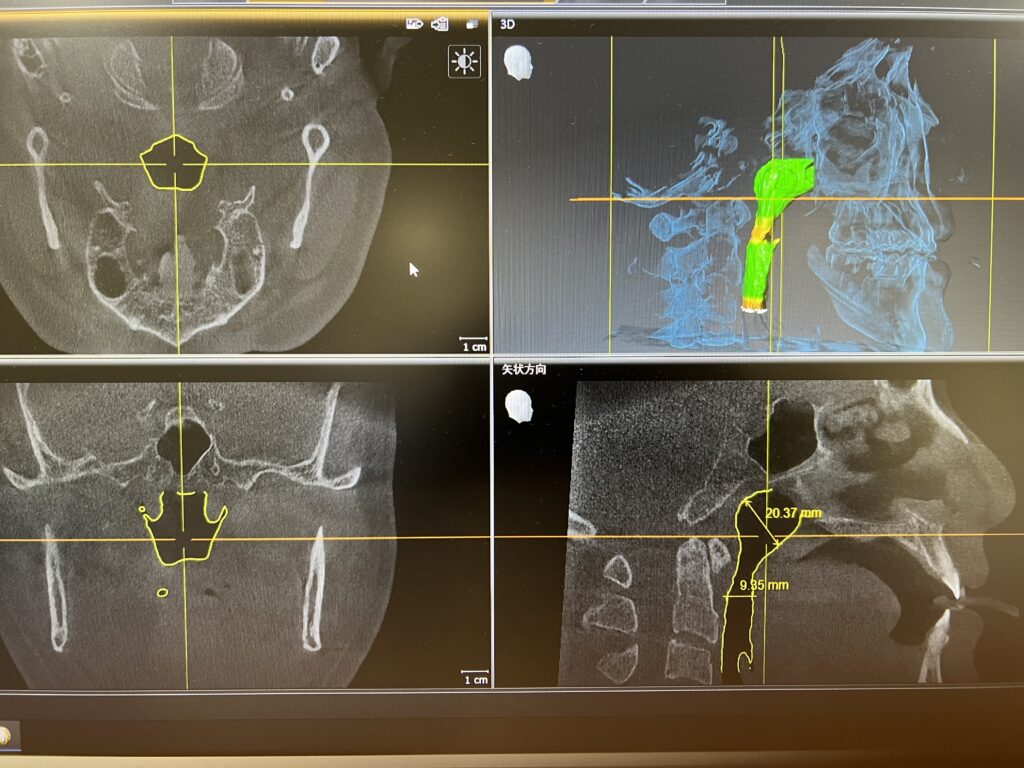

気道解析

CTの撮影範囲を広げることによって咽頭の方まで見ることが可能となり、そこから気道の広さや形などを確認出来ます。

これによって、現代病として突然死などが問題になっている睡眠時無呼吸症候群(←押して頂くと睡眠時無呼吸症候群のページへ)の可能性を見たり、睡眠時無呼吸用の口腔内装置を入れて気道がどう変わるかなどを確認することが可能です。

また、小児期で顎や顔面の成長が弱く、気道が狭くなっていることが確認できた場合は筋機能訓練や、プレオルソを含めた小児矯正治療(←押して頂くと小児歯科・小児矯正ページへ)などで成長を促進させ気道を広くすることによって頭や体の成長につなげることもあります。

このように気道の状態を3次元的に見やすくして、どこが狭いかなども把握できます😲